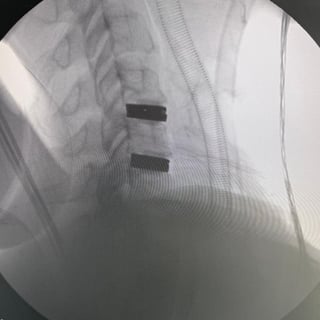

Pre-Op

Image: Pre-operative x-ray of disc degeneration at C3-C4 level in the cervical spine.

Image: Post-operative x-ray of Triadyme-C at C3-C4 level in the cervical spine.